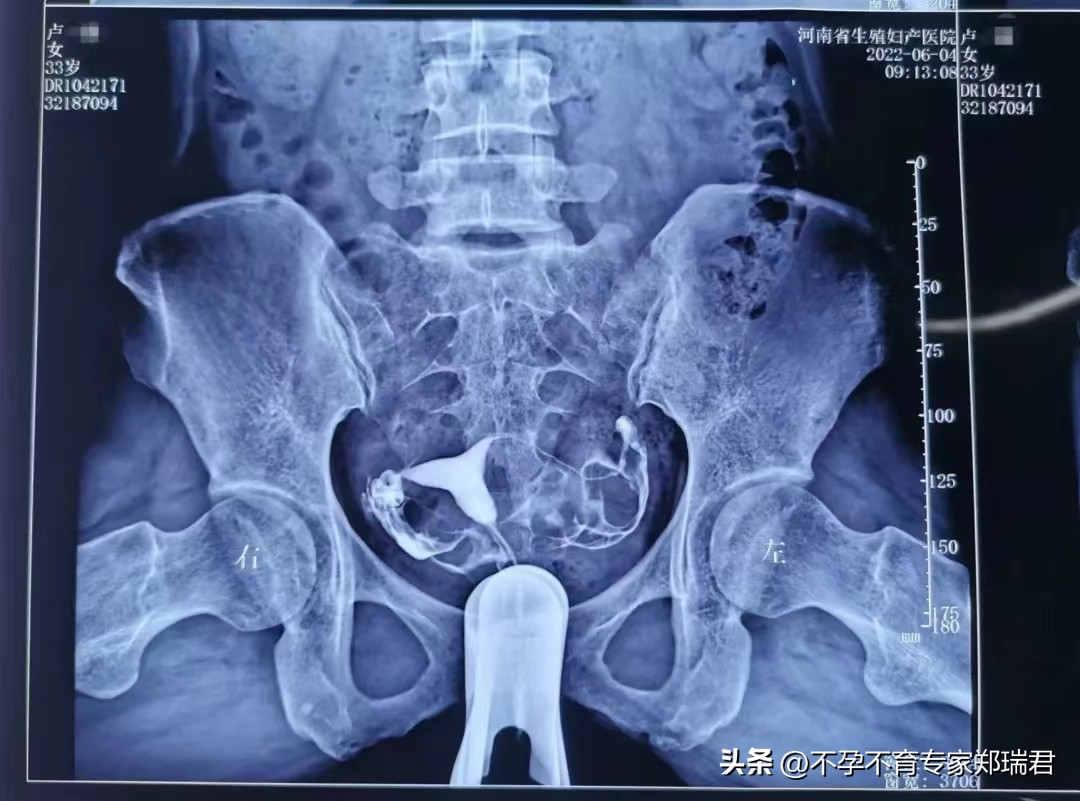

2022年6月4号复查子宫输卵管造影示:宫体右偏,双侧输卵管已通: